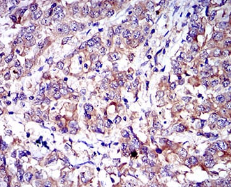

IHC    1/200 - 1/1000